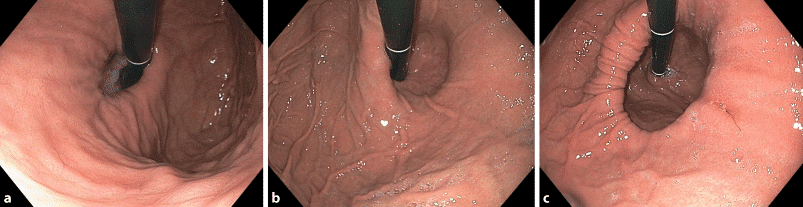

- Πρώτη εξέταση συνήθως: ΓΑΣΤΡΟΣΚΟΠΗΣΗ (EGD)

- Εκτιμά βλεννογόνο (οισοφαγίτιδα/Barrett), μέγεθος/τύπο κήλης, οισοφαγικό στόμιο (Hill grade)

- Απαραίτητη σε red flags, ανθεκτικά συμπτώματα, >50–60 ετών, προεγχειρητικά

- Ενδοσκόπηση οισοφάγου-στομάχου

- Πρέπει να προηγείται σε όλους τους ασθενείς.

- Επιβεβαιώνει τη Γαστροοισοφαγική Παλινδρόμηση, ελέγχει τυχόν βλεννογονικές ανωμαλίες και επιτρέπει την λήψη βιοψιών.